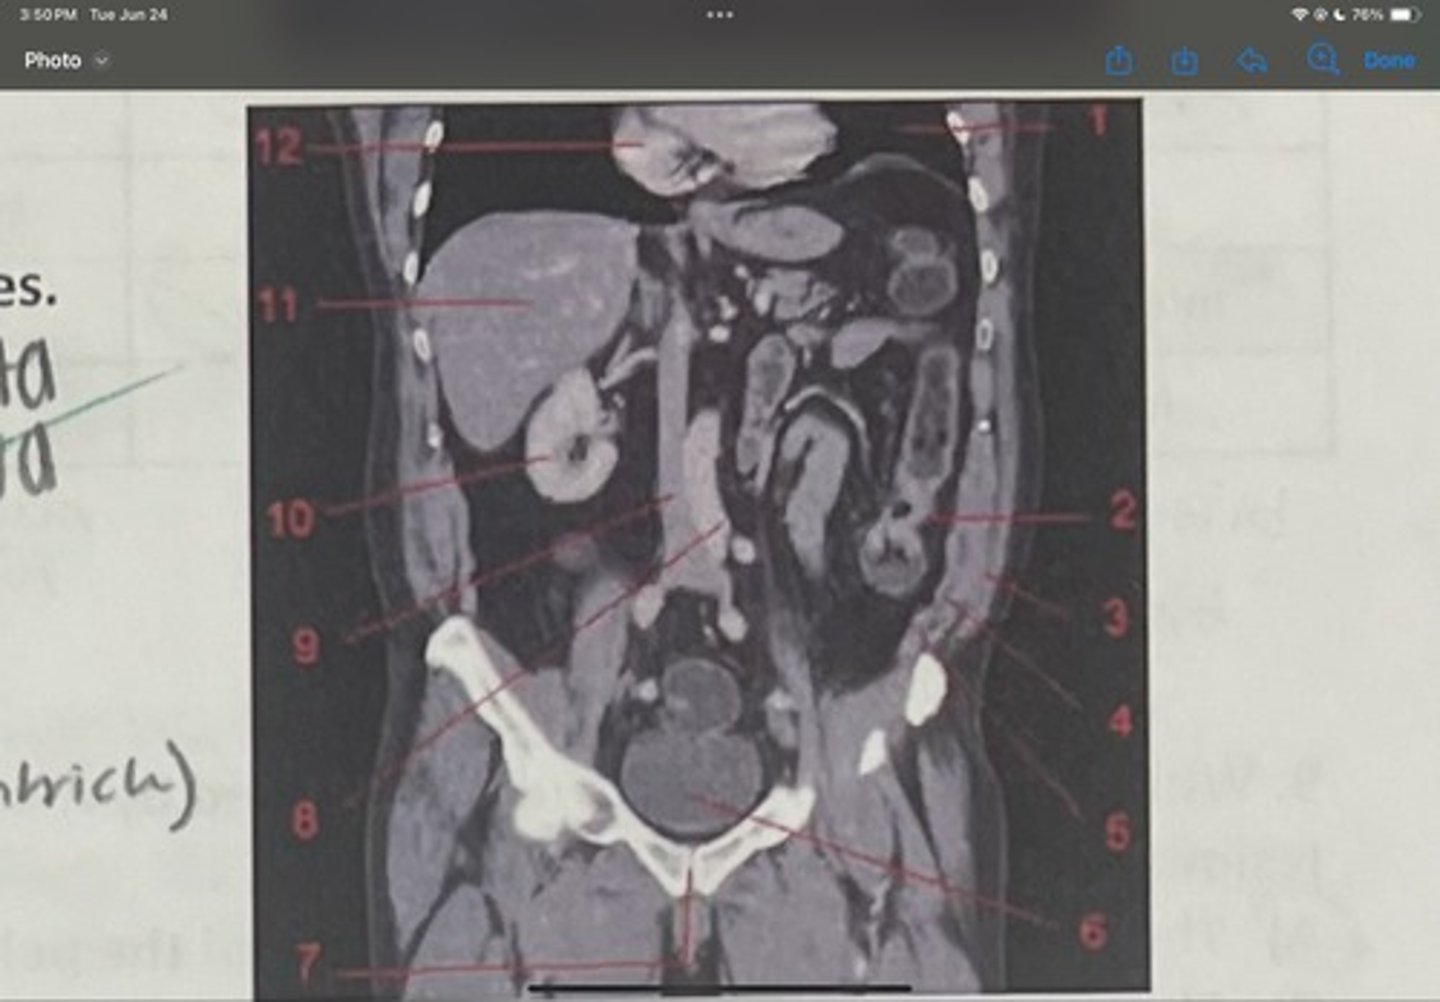

What is 1

Descending colon

What is 2

External oblique

What is 3

Internal obliques

What is 4

Transversus abdominis

What is 5

Bladder

What is 6

Pubic sysmphysis

What is 7

Abdominal aorta

What is 8

Inferior vena cava

What is 9

Right kidney

What is 10

Liver

What is 11

Heart (right ventricle)

What is 12

Subcostal nerve (T12)